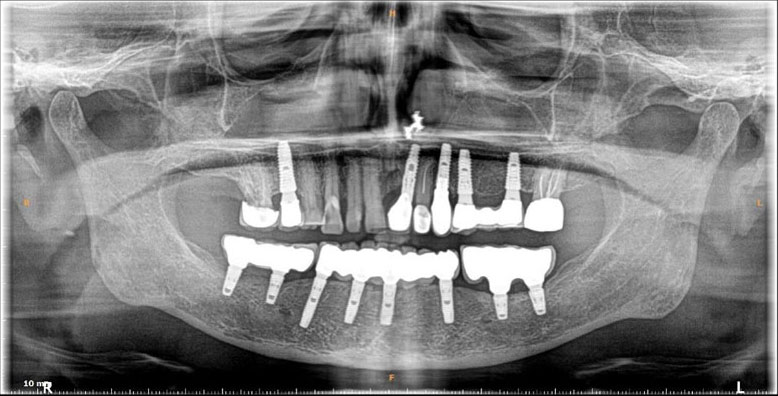

Dental Implants

Dental implants are artificial tooth roots use to replace decayed or missing teeth. They are a popular and effective long-term solution, dental implants are placed into the jawbone, providing a stability for replacement teeth.